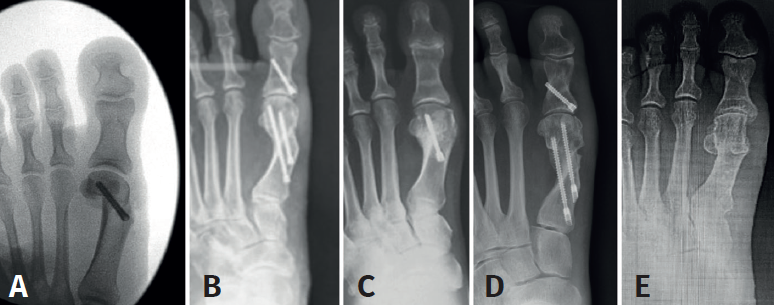

Mediante abordaje de 5 mm a nivel plantar proximal al bunion se realiza capsulotomía y exostectomía (Figuras 1A, B y C). Por otro abordaje de 3 mm realizado a 5 mm dorsal y distal del primero y a 15 o 20 mm proximal a la superficie articular (entre 7 y 10 mm del centro geométrico de la cabeza), extraarticular y equidistante a la cortical dorsal y plantar, se procede al tallado de la osteotomía de Chevron con fresa Isham larga (2,0 × 12 × 65 mm), (Figura 1D). Con la fresa dirigida, preferentemente, perpendicular al cuarto metatarsiano y llevándola ligeramente a plantar o dorsal según quisiéramos descender o elevar, respectivamente, la cabeza metatarsiana, perforamos el primer metatarsiano. En modelos sin fijación, elegimos esta dirección hacia proximal para lograr un leve acortamiento, que relaja la articulación metatarsofalángica y reduce las posibilidades de pérdida de corrección de la cabeza (Figura 2). En modelos con fijación se dirige más hacia distal, con referencia en la diáfisis del segundo metatarsiano o incluso perpendicular al primer rayo. Realizamos el corte dorsal casi vertical y el corte plantar lo más horizontal posible (paralelo al suelo), con dirección de distal a proximal, tratando de que esta rama sea más larga que la anterior. Se puede lograr de forma adicional corrección del DMAA. Una vez completa la osteotomía, se desplaza a lateral manualmente bajo visión radioscópica hasta que se logra una posición satisfactoria. No se coloca osteosíntesis. Se procede a la adición de otros gestos percutáneos de ser necesarios (liberación lateral de partes blandas, osteotomía de Akin, osteotomías de metatarsianos o dedos menores) (Figura 3).

Los estudios y/o técnicas mínimamente invasivas relevantes sobre Chevron percutánea con fijación son: PeICO (Del Vecchio et al.), PERC (Hernández et al.), PECA (Lee et al.), MICA (Redfern-Vernois)(6,18,19).

Del Vecchio, en una primera publicación donde evalúa el resultado radiográfico de la técnica PeICO (percutaneous, intra-articular, Chevron osteotomy), concluye no encontrar acortamiento del primer metatarsiano ni recurrencias, y corrección satisfactoria de los valores angulares. En una segunda publicación más actual y de estudio cadavérico arroja que esta técnica es segura, no encontrando daños vasculonerviosos o tendinosos; utiliza un tornillo de fijación sin atravesar la cortical lateral y es reproducible en cirujanos experimentados en técnica MIS de pie, imitando el Chevron abierto.

Una MICA (minimally invasive Chevron Akin) es una técnica que se aleja del centro geométrico de la cabeza hacia proximal, es extraarticular, se realiza en el cuello del metatarsiano, utiliza 2 tornillos sin cabeza de fijación y se asocia con una osteotomía de Akin. Sus autores publican buenos y excelentes resultados, sin rigidez metatarsofalángica y extienden la indicación hasta el hallux valgus grave, ya que proponen hasta un 100% de desplazamiento de la cabeza metatarsiana.

Una PERC (percutaneous extra-articular reverse-L Chevron osteotomy) realiza la osteotomía en el mismo sitio que la MICA, pero la diferencia es que fija con 1 tornillo de dorsal a plantar.

Una PECA (percutaneous Chevron/Akin) es técnicamente lo mismo que la MICA.

Todos estos estudios arrojan resultados radiográficos similares en cuanto a la corrección de los valores angulares; publican buenos índices de consolidación, bajas tasas de complicaciones, satisfactorio rango de movilidad metatarsofalángico y se los considera procedimientos reproducibles en cirujanos de pie y cirujanos experimentados en técnica MIS.

Como vemos, la sugerencia de algún tipo de estabilización debido al riesgo de desplazamiento de la cabeza metatarsiana, menor dolor y edema es una constante en las mencionadas publicaciones. Este concepto es discutible debido a que la osteotomía de tipo Chevron realizada con la rama plantar larga y paralela al piso es intrínsecamente estable y compatible con un postoperatorio de carga precoz (Figuras 4A, B y C) al igual que las osteotomías “con fijación”(17). Los problemas relacionados con el uso de osteosíntesis en las osteotomías metatarsianas ascienden al 10-15% en diferentes series(3,9,11).

Uno de los aspectos importantes en cuanto a la posición de la cabeza metatarsiana es el referente al plano sagital. Pocos trabajos de tratamiento de hallux valgus evalúan el ascenso de la cabeza. En este grupo de pacientes hemos observado que el ascenso de la cabeza es solo de 1,03 mm como promedio y no encontramos en la evolución alguna repercusión clínica asociada con dicho ascenso (Figura 5). Otro aspecto de la osteotomía en Chevron es que históricamente ha sido usada para la corrección de hallux valgus leves a moderados por su ubicación intraarticular, como es la forma clásica abierta o la moderna PeICO(11,12,13). Una de las modificaciones propuestas en este trabajo es hacer la osteotomía PECU a 7 o 10 mm proximal al centro geométrico de la cabeza (ubicación extraarticular), lo que nos permite un mayor desplazamiento y mejora el poder de corrección, asemejándose a una osteotomía diafisaria, como describen autores como Redfern, Vernois, Lee, Hernández, Bauer o Laffenétre en modelos de Chevron percutánea con fijación(3,4,5,9). En este trabajo fueron tratados hallux valgus graves (HV°> 40° e IM° > 16°) de forma satisfactoria.

Las complicaciones asociadas con el Chevron incluyen la necrosis avascular(1,12). En nuestro trabajo no hubo casos y creemos que esto se debe a que, al realizar los gestos de forma percutánea y más proximales, Chevron + abductor + Akin, el daño vascular es menor. Esto también explicaría que las osteotomías tengan un alto porcentaje de consolidación (Figura 6).

Nuestro modelo PECU puede hoy ser comparado con series con fijación, arrojando resultados similares(2,9,10,11,12,13)(Figura 7).